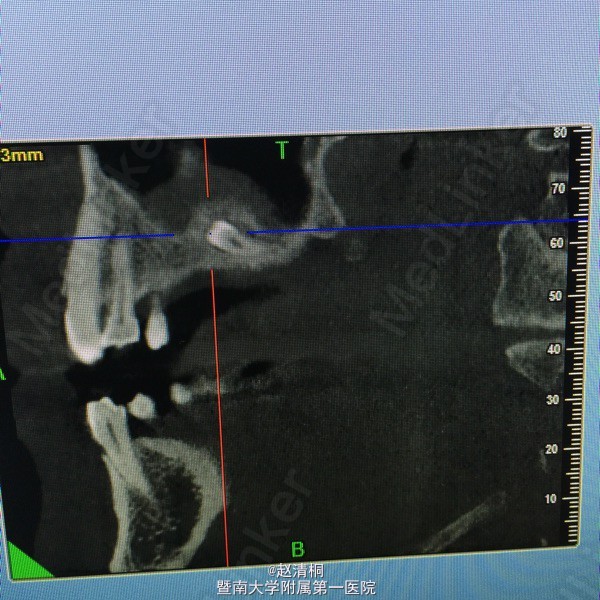

CBCT显示只有3mm骨量,上颌窦内侧壁有一多生牙,没有CT,这种病例不敢种的。

转透骨皮质后,即用上颌窦提升工具从小于植体直径慢慢敲入,提升后,植入10mm种植体。